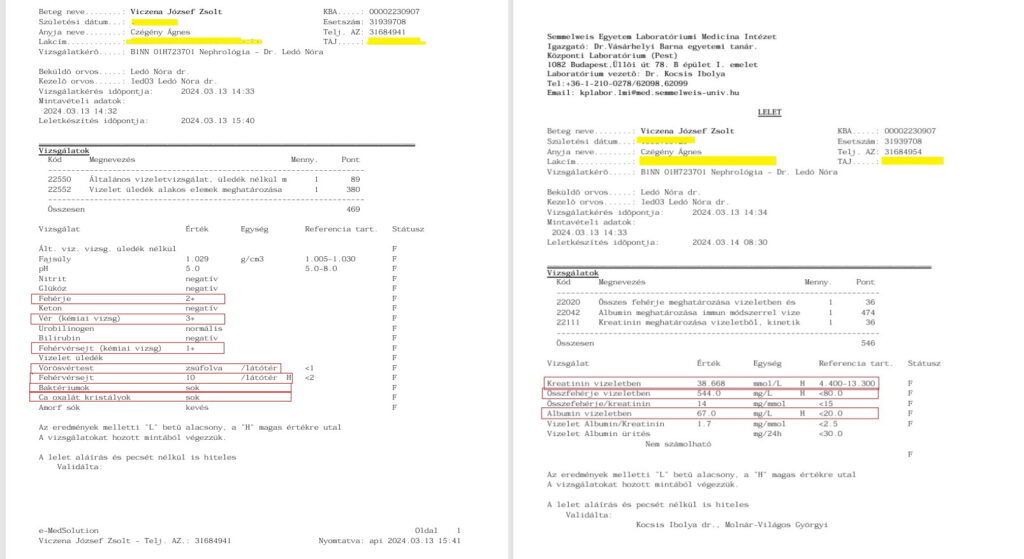

A fiam rohant Jordán doktor sürgősségi beutalójával az I. Belgyógyászati Klinika nefrológiai ambulanciájára, hogy felvegyék. Dr Ledó Nóra nefrológus ambulánsan „felvette”. Majd annak ellenére, hogy Zsolt közölte vele, hogy 6. napja szed antibiotikumot, Supraxot (Cefixime), nem érdekelte, szedése ellenére utasította fiamat tenyésztéshez vizeletminta leadására (durva szakmai hiba). Természetesen így a baktériumtenyésztés negatív lett. Ezért a fiamnak nem adott antibiotikumot, és kijelentésszerűen beírta az EESZT-jébe, hogy „uroinfekció nincs, antibiotikum adása nem indokolt”. Pedig hozott – 2 napos – leletén 650 vörösvértest/látótér szintű vérvizelés, fehérjevizelés volt, az általa készítetten pedig „sok baktérium/látótér” – az antibiotikum szedés ellenére. Emellett a klinikai tünetek: elviselhetetlen vesefájdalom, csupán éjszaka 9-10 vizelet, hányinger, napi 5-6 hasmenés. Ezek ellenére Ledó Nóra nem vette fel a fiamat kórházi kezelésre és nem adott IV antibiotikumot, pedig ilyen urológiai-nefrológiai állapottal napokon belül kórházban kezelnek mindenkit, minden civilizált országban – ez meg a főváros I. számú Belgyógyászati Klinikája!

Konzultáció dr. Ledó Nóra nefrológussal, vizeletvizsgálat, mellkas röntgen. A kórházba nem vette fel Zsoltot még most sem, pedig a fiam azt ismételgette, „De én akut állapotban vagyok, tudom milyen amikor nagy baj van és amikor nincs, ez egy nagyon súlyos akut állapot!” Nem érdekelte. Pedig most már „baktériumok: zsúfolva/látótér” volt az eredmény, vagyis maximális baktériumvizelés. Úgy hogy csupán egy-két napja fejezte be az ügyeleten felírt Suprax antibiotikumot. Csoda, hogy a baktérium bejelzett, ráadásul ennyire, mert az antibiotikum teljesen „meghamisítja” a sima vizeletvizsgálatot is, ezért írnak elő 4-8 nap szünetet orvosok újabb tenyésztések előtt – van olyan antibiotikum, amelyik 15-6 nap után ürül csak ki az ember szervezetéből teljesen… (pl. azitromicin)

11./ Március 13. Újra Semmelweis Egyetem I. sz. Belgyógyászati és Onkológiai Klinika: Dr Ledó Nóra

A fiam látta, hogy reggel az EESZT-be bejegyezte Ledó Nóra, hogy nincs nefrológiai teendő, a továbbiakban keresse fel háziorvosát, akinél 3-4 havonta csináltasson vizelet és vérvizsgálatot. Mintha a fiamnál minden rendben lett volna! Pedig ekkor már több mint 1 hónapja szenvedett kezeletlenül, nézni alig lehetett: Éjjelente 8-10 vizelet, délelőtt 5-6 hasmenés, 0-24 kétoldali elviselhetetlen vesefájdalom, hőemelkedések, hányinger, gyomortáji fájdalom, nagyon magas pulzus. (Súlyos vesemedence-gyulladás tünetei!) Éppen amikor a fenti sorokat Dr Ledó beírta az EESZT-be és lezártnak tekintette Zsolt esetét, visszatért a vérvizelés!

Rohantunk Budapestre a vizeletmintával, leadni a Semmelweis laborba. Az eredmény sokkoló lett:

A vizeletet Dr Ledó Nóra eredetileg a portára (!) akarta velünk leadatni. Nem tudom, hallott-e már valaki ilyet?! Persze a laborba vittük és megvártuk míg adminisztrálják, hogy biztos ne történjen olyan véletlen, hogy eltűnik. Ezután siettünk magánúton (abszurdum) szívultrahangra, ahol 29 ezer forintot fizettünk ki a cégnek, mert Dr. Ledó azt mondta a komoly baloldali mellkasi-szívtáji és lapockatáji-háti fájdalommal küzdő fiamnak – ami tünetek egyszerre jelentek meg a vérvizeléssel, vesefájdalommal, magas pulzussal – hogy „Nem tudom elintézni, a klinikán 4-5 hetet kell várni egy szív ultrahangra”. Teljesen gúnyt űzött az orvosnő a fiam súlyos állapotából. Ekkor be kellett volna menni az igazgatóhoz, hogy egy SOTE Belklinika hogyan teheti ezt meg akut betegekkel? Talán ha felvette volna a borzalmas állapotú fiamat a kórházba, egy napon belül is megtörténhetett volna TB-finanszírozottan. Visszatérve az eredményre, a vizelet 10 pozitív eltérést mutatott, mivel nehéz lehet az apróbetűket olvasni, az alábbiakban leírva is közlöm:

– 2 keresztes fehérjevizelést

– 3 keresztes vérvizelést

– vörösvértestek zsúfolva/látótér! (egy másik ottani nefrológus azt mondta, 10-15 vvt/látótér értékekkel találkozik a napi gyakorlatban – Zsoltnak 100 és 1000-szerese volt ennek, ismét!)

– fehérvérsejt (genny) 10/látótér (ref. érték: 2) – ezúttal már genny is volt a vizeletben, amit a doktornő gátlástalanul letagadott nekem

– baktériumok sok/látótér

– Calcium-oxalát kristályok sok/látótér.

– Albumin a vizeletben több mint 3-szorosa

– Összfehérje a vizeletben több mint 7-szerese (a vese átengedi a fehérjét!)

– Kreatinin a vizeletben 3-szorosa a normális értékek felső határának.

Visszatérve a mintákra, párhuzamosan leadtunk egy mintát a Synlab-hoz is, kvantifikálja az eredményt ellentétben más leletekkel. Szintén alarm eredmény!

Március 14-én kiállított közben egy olyan leletet, ahol a 10 pozitív, köztük súlyos nefrológiai paraméterekből, kiválasztott mindössze 2-t, a „vvt zsúfolva/látótér” és a „sok kristály” megállapításokat, a maradék 8-ról (például 7-szeres fehérjevizelés, gennyvizelés, baktériumvizelés) pedig nem írt semmit. Több liter víz fogyasztásáról írt, éjszaka is javasolva (miközben a fiamtól tudta, hogy éjszaka 9-10 vizelete van, vagyis így sem tud aludni, óránként felébred emiatt és a fájdalom miatt), továbbá „kezelése” a fiam számára közel 1,5 hónap kezeletlenség után, hogy kerülje a spenótot, rebarbarát, málnát, csokoládét, c-vitamint. És felháborodott, hogy személyesen felmentünk a súlyos leleteredmény után másnap 14-én, egy három napos ünnep előtt és nem telefonon akartuk letudni a fiam állapotát.